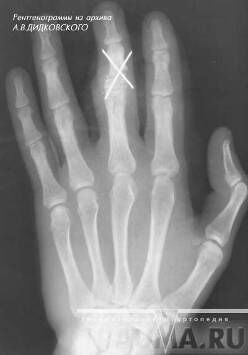

Переломы второй, третьей, четвертой и пятой пястных костей встречаются несколько реже. Возникают они под воздейтвием прямой травмы кисти и реже при ударе кулаком или при падении на кулак. Часто возникают переломы не одной, а нескольких пястных костей. Смещение отломков может быть незначительным, так как пястные кости фиксированы одна к другой связками и мышцами. Но чаще, особенно при множественных переломах, отломки смещаются по длине под углом, открытым в ладонную или тыльную стороны кисти. Пациент жалуется на боли в кисти, ладони, усиливающиеся при попытке сжать кисть в кулак. Для определения места перелома пациента тянут за палец, при переломе соответствующей пястной кости, боль резко усиливается. Диагноз уточняют при помощи рентгеновских снимков(рис.4) (17, с.145).

Рисунок 4 - Перелом головки 3 пястной кости с небольшим смещением, в двух проекциях